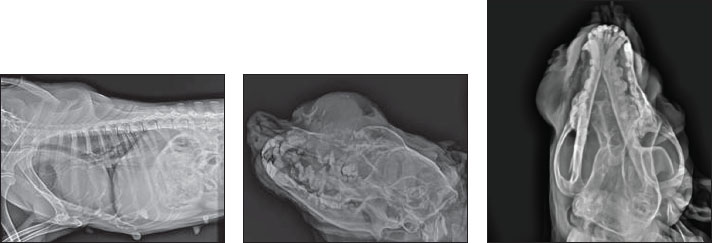

Fig. 2. Cytology reveals several mesenchymal cells without malignant features, including cells with a round morphology and cytoplasm vacuoles, coarse chromatin, or nucleoli. The radiology displayed an osteolytic expansile lesion, proliferative periosteal reaction, irregular margin, and stippled to speculated columnar periosteal reaction (Fig. 3). The tumor originated from the end of the nostrils to the ocular region. The transition zone is poorly demarcated from normal bone.

Fig. 3. X-ray showing osteolytic expansile lesion proliferative periosteal reaction irregular margin and stippled to speculated columnar periosteal reaction. The frontal bone, nasal bone, and maxilla depicted gross destruction. These are features of aggressive bone lesions. The differential diagnosis included multiple myeloma, Osteoma, Squamous cell carcinoma, malignant melanoma, acanthomatous ameloblastoma, and fibrosarcoma. Biopsy sample obtained from the rostral aspect of the mass shows cartilaginous tissue in the center of the tumor, and the chondrocytes are normal. There was no malignant tumor, and the pathological assessment showed a histiocytoma. Surgical approach was performed to remove the expansile tumor (Fig. 4 Post-op), general anesthesia was induced by ketamine-Diazepam (5 mg.kg-1, 0.5 mg.kg-1) and Isoflurane maintenance by 3% MAC (minimum alveolar concentration).